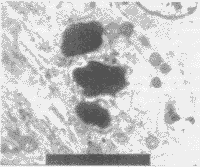

空载质粒对照组胚脑细胞超微结构正常,未观察到凋亡细胞。转基因组可见脑细胞间缝隙连接减少,细胞形态变异,电子密度增高;溶酶体和空泡增多,线粒体肿胀或固缩,内质网和高尔基体亦有不同程度肿胀,核糖体不丰富;细胞核形态不规则,出现切迹;核内异染色质增多,浓缩成团块状和边缘化,核仁分裂。观察到凋亡细胞(图5和图6)。

图5 第3组,正常脑细胞,透射电镜,×10000

图6 第4组,胚脑细胞凋亡,透射电镜,×10000

2.4.3 透射电镜观察